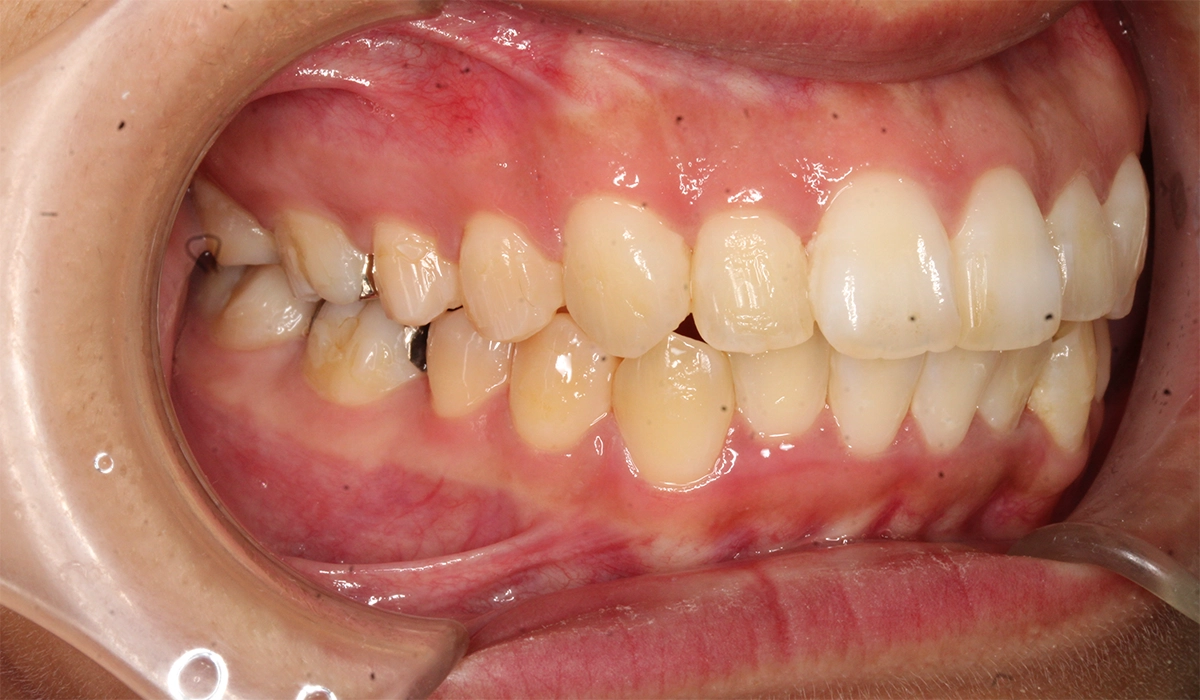

術前:右側